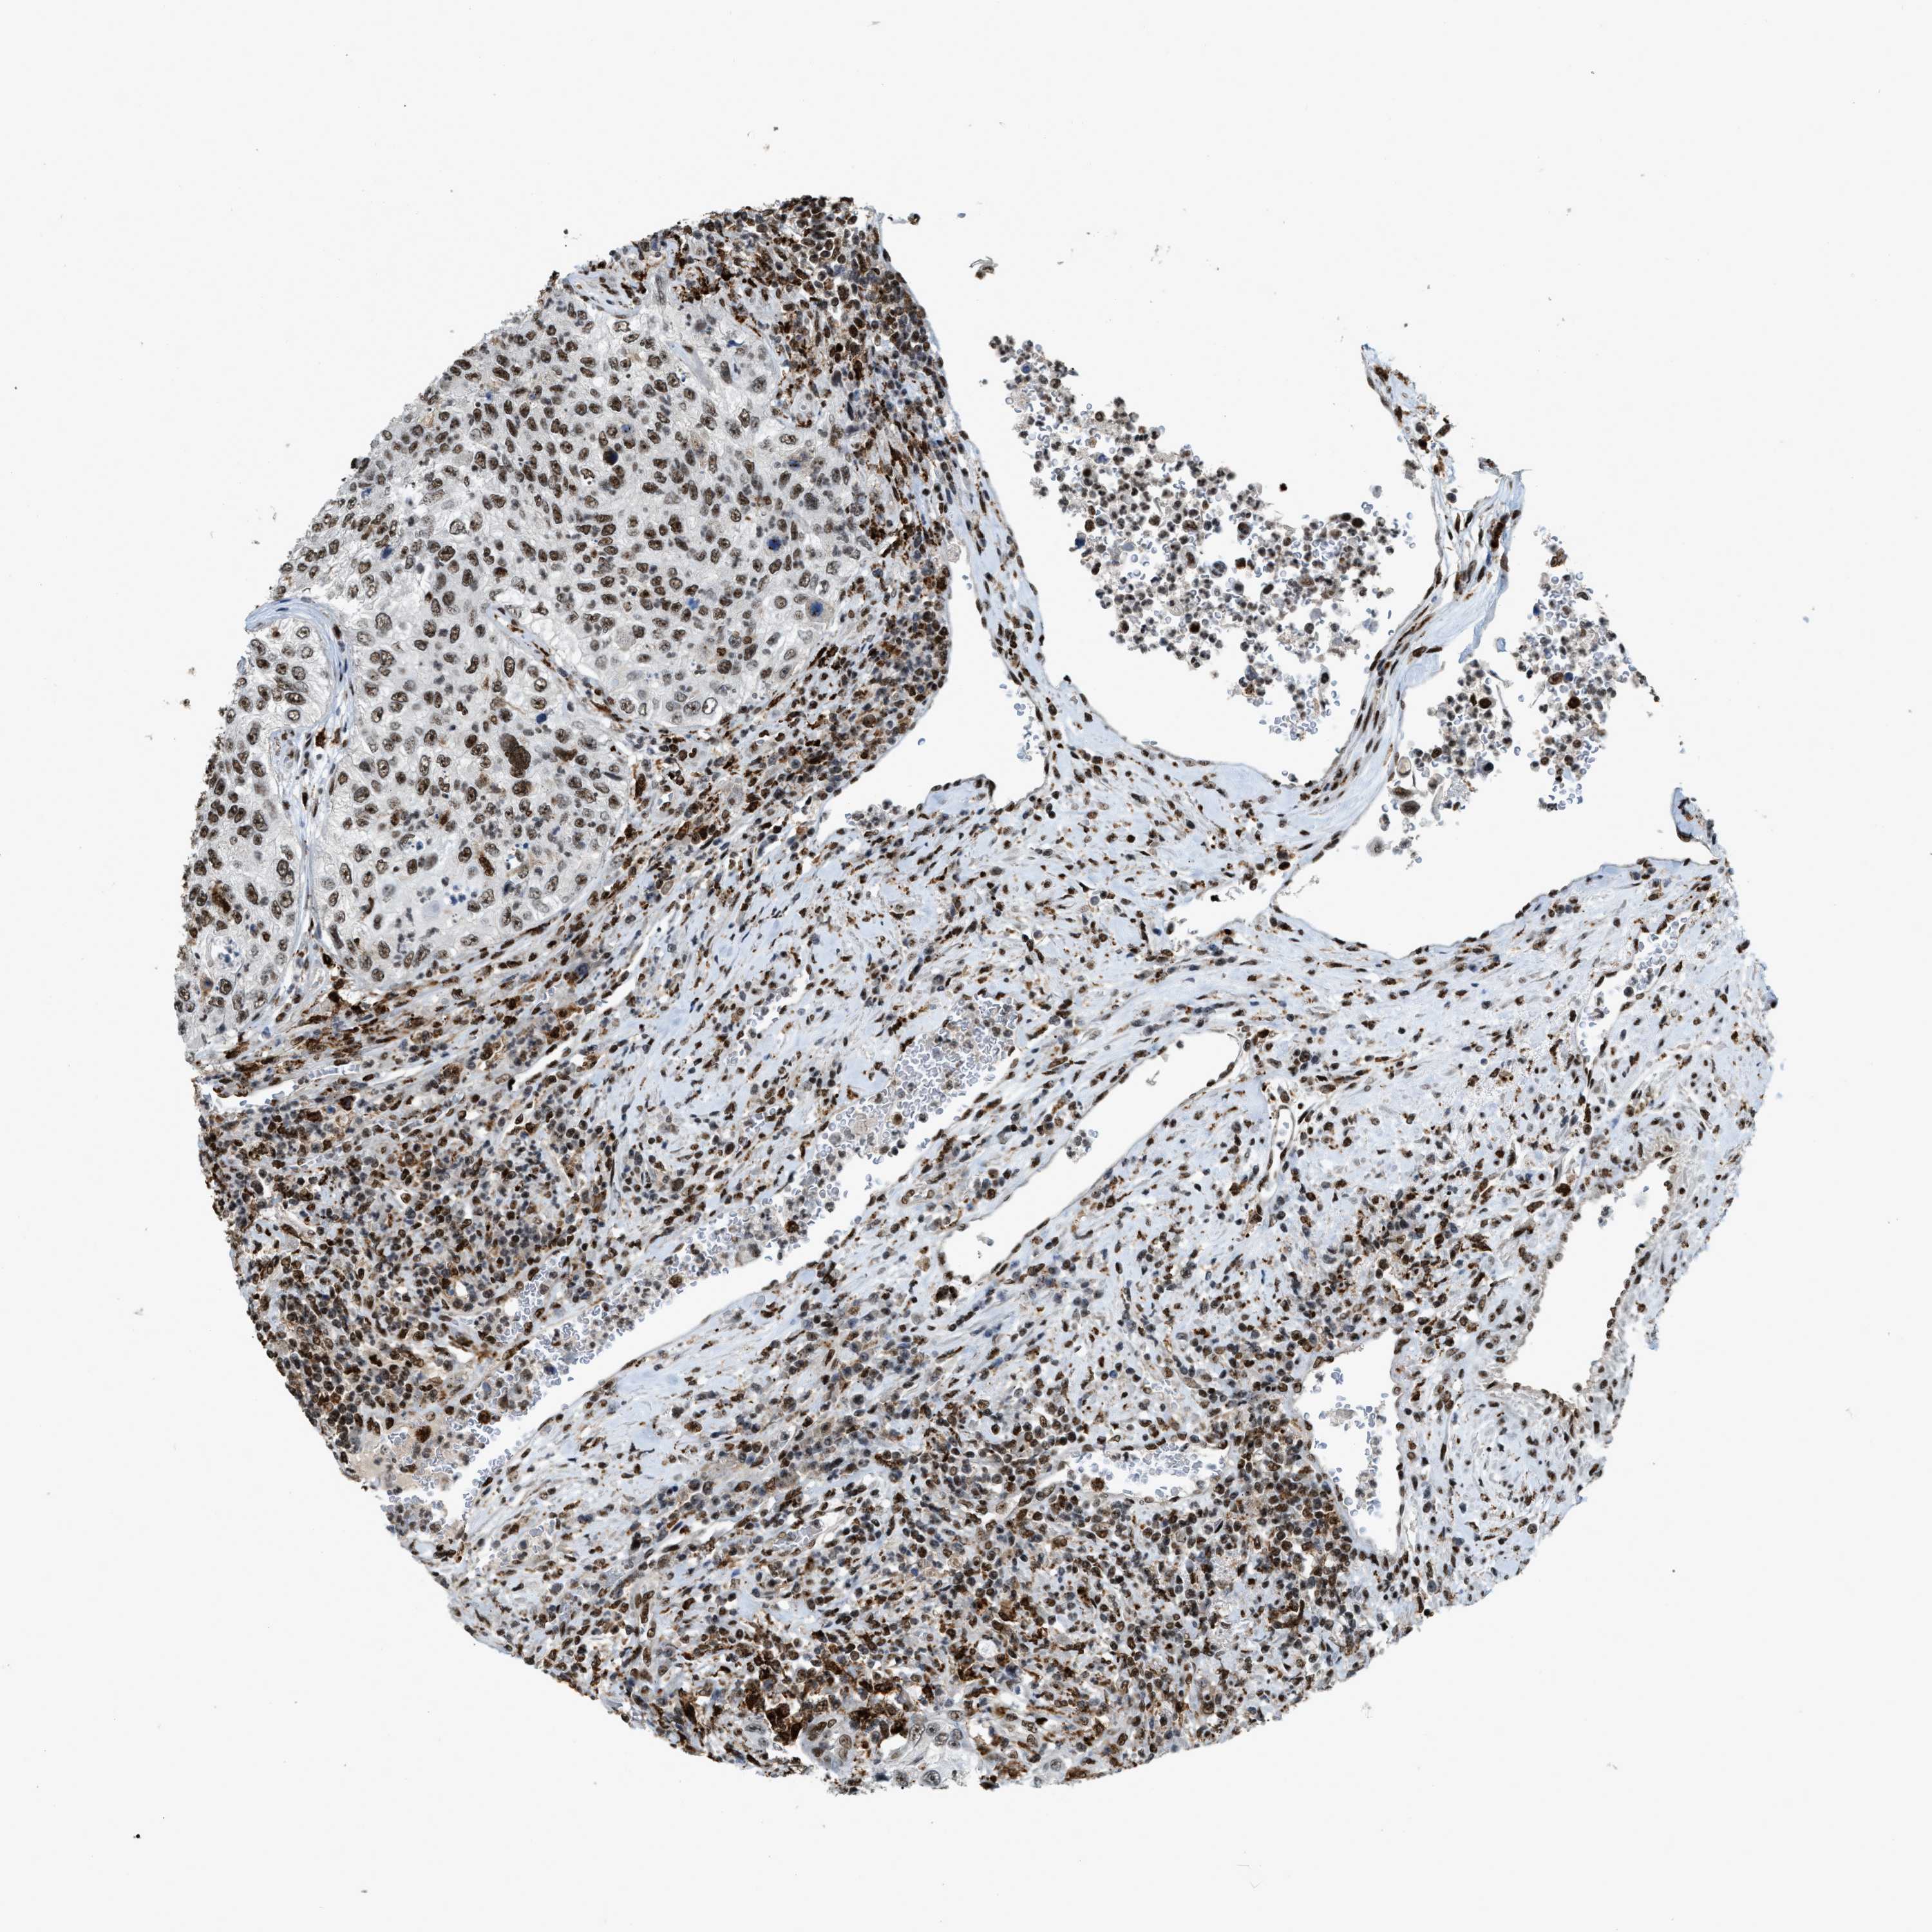

UROTHELIAL CANCER - Protein expressioni

A mouse-over function shows sample information and annotation data. Click on an image to view it in a full screen mode. Samples can be filtered based on level of antibody staining by selecting one or several of the following categories: high, medium, low and not detected. The assay and annotation is described here.

Note that samples used for immunohistochemistry by the Human Protein Atlas do not correspond to samples in the TCGA dataset.

Antibody stainingi

Antibody staining in the annotated cell types in the current human tissue is reported as not detected, low, medium, or high, based on conventional immunohistochemistry profiling in selected tissues. This score is based on the combination of the staining intensity and fraction of stained cells.

Each image is clickable and will lead to virtual microscopy that enables deeper exploration of all samples and also displays staining intensity scores, fraction scores and subcellular localization as well as patient and tissue information for each sample.

Antibody HPA019841

Antibody HPA019859

Antibody HPA029912

Staining

High

Medium

Low

Not detected

Intensity

Strong

Moderate

Weak

Negative

Quantity

>75%

75%-25%

<25%

None

Location

Nuclear

Cytoplasmic/membranous

Cytoplasmic/membranous,nuclear

Urothelial carcinoma, Low grade

Urothelial carcinoma, High grade